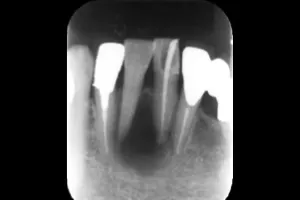

Case.01

治療前

治療中

治療後

治療前後の比較

| 治療名 | 根管治療 |

| 患者様情報 | 76歳 女性 |

| 担当医 | 岸田 義弘 先生 |

| 費用 | 1根管33,000円~ |

| 主訴 | 下の前歯の歯茎が腫れて痛い |

| 治療期間 | 約2ヶ月 (月1〜2回) |

| 治療内容 | 1.歯髄が生きているかどうかの確認 2.根管治療 3.修復治療 4.経過観察 治療の結果腫れもなくなり、歯の移動も戻りました。 |

| 治療のリスク | 術後2~3日後に痛みが出ることあります。術後1年程経過を追って、治癒傾向があれば経過観察、病変の拡大を認めるならば外科的対応になる可能性があります。 |